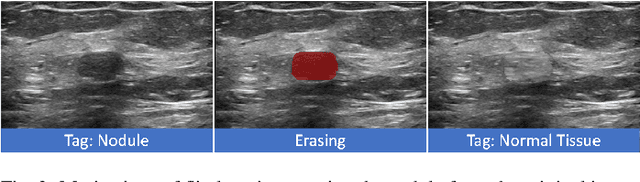

Abstract:Accurate segmentation of nodules in both 2D breast ultrasound (BUS) and 3D automated breast ultrasound (ABUS) is crucial for clinical diagnosis and treatment planning. Therefore, developing an automated system for nodule segmentation can enhance user independence and expedite clinical analysis. Unlike fully-supervised learning, weakly-supervised segmentation (WSS) can streamline the laborious and intricate annotation process. However, current WSS methods face challenges in achieving precise nodule segmentation, as many of them depend on inaccurate activation maps or inefficient pseudo-mask generation algorithms. In this study, we introduce a novel multi-agent reinforcement learning-based WSS framework called Flip Learning, which relies solely on 2D/3D boxes for accurate segmentation. Specifically, multiple agents are employed to erase the target from the box to facilitate classification tag flipping, with the erased region serving as the predicted segmentation mask. The key contributions of this research are as follows: (1) Adoption of a superpixel/supervoxel-based approach to encode the standardized environment, capturing boundary priors and expediting the learning process. (2) Introduction of three meticulously designed rewards, comprising a classification score reward and two intensity distribution rewards, to steer the agents' erasing process precisely, thereby avoiding both under- and over-segmentation. (3) Implementation of a progressive curriculum learning strategy to enable agents to interact with the environment in a progressively challenging manner, thereby enhancing learning efficiency. Extensively validated on the large in-house BUS and ABUS datasets, our Flip Learning method outperforms state-of-the-art WSS methods and foundation models, and achieves comparable performance as fully-supervised learning algorithms.